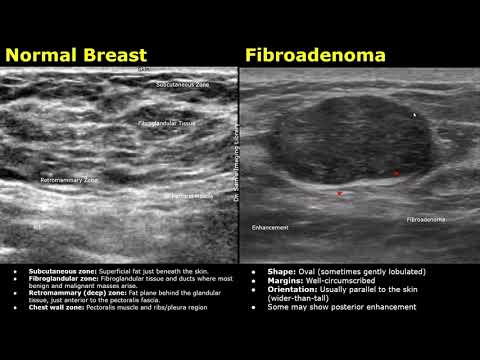

Brustultraschall: Normalbefund vs. Fibroadenom | Ultraschalluntersuchung gutartiger Brustknoten/T...